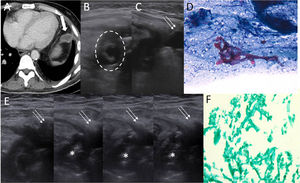

La mucormicosis pulmonar es una infección oportunista causada por hongos Mucorales. Se adquiere por inhalación de espora y se caracteriza por invasión de estructuras vecinas y por una elevada mortalidad1. Debe iniciarse el tratamiento precozmente, el cual consiste en la administración de anfotericina B liposomal y un desbridamiento quirúrgico amplio2. Presentamos el caso de un paciente de 50 años inmunodeprimido que como complicaciones había presentado una neumonía necrosante por mucormicosis pleural y pericárdica, requiriendo lobectomía superior izquierda y pericardiectomía con epiploplastia. En una tomografía computarizada de control se le detectó una colección líquida con realce periférico en la grasa interpuesta en el mediastino en relación con la epiploplastia (fig. 1A). Se amplió el estudio con una ecografía torácica que evidenció una colección anecoica (fig. 1B) que se puncionó (fig. 1C), obteniéndose un material blanquecino que se remitió para estudio. La citología evidenció estructuras micóticas irregulares compatibles con mucormicosis (fig. 1D). Se realizó, asimismo, punción torácica para instilación de anfotericina B intracavitaria (fig. 1E) dado el mal estado del paciente, que no podía someterse a una intervención quirúrgica. Se administró también anfotericina B intravenosa y, dada la buena evolución clínica, el paciente pudo someterse a la resección quirúrgica del epiplón, siendo la resección quirúrgica del tejido afecto el tratamiento de elección. La pieza quirúrgica evidenció fragmentos micóticos desvitalizados (fig. 1F).

A) TC torácica axial en ventana de partes blandas que muestra una colección líquida con realce de sus paredes en mediastino, a nivel supradiafragmático (flecha gruesa), donde se había interpuesto la grasa proveniente del epiplón (epiploplastia) a raíz de la pericardiectomía previa. B) Ecografía torácica que muestra colección anecoica en grasa mediastínica con imagen circunferencial ecogénica en su interior (círculo discontinuo). C) Punción percutánea de la colección mediante aguja 20G (flechas finas). D) Muestra citológica que evidencia fondo necrótico con celularidad inflamatoria constituida por leucocitos polimorfonucleares, así como estructuras micóticas irregulares compatibles con mucormicosis. E) Ecografía torácica que muestra punción torácica (flechas finas), con instilación progresiva de anfotericina B intracavitaria (asterisco). F) Pieza quirúrgica que evidencia nódulo pleural necrótico con infección micótica morfológicamente compatible con mucormicosis.